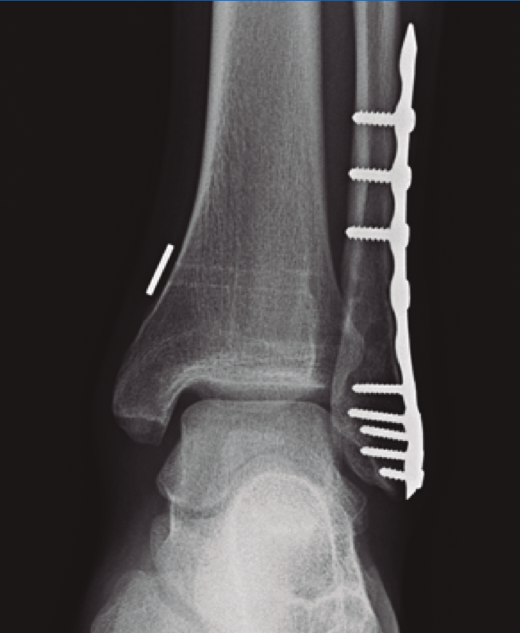

Figura 3. A: fractura suprasindesmal del peroné sintetizada con placa tercio de caña y 2 tornillos transindesmales; B: mismo caso a los 3 años de seguimiento con rotura de tornillos y apertura de la sindesmosis con cambios degenerativos tibioastragalinos.